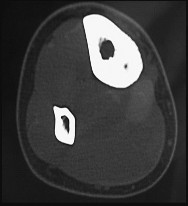

Question 42

A revision total hip arthroplasty is performed for a fractured modular neck. Examination of the taper junction reveals black debris and pitting. What is the primary initiating mechanism of corrosion at the modular taper junction of a titanium stem and cobalt-chrome head?

Explanation

Fretting corrosion (mechanically assisted crevice corrosion) is the primary initiating mode of failure at modular junctions in total joint arthroplasty. Micro-motion mechanically disrupts the protective passivation (oxide) layer, which then allows crevice and galvanic corrosion to occur.